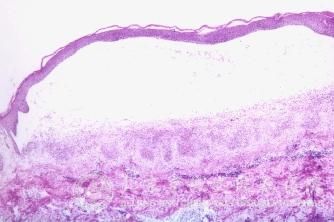

传染性湿疹样皮炎的发病机制是什么?传染性湿疹样皮炎是由各种原因引起的皮肤病,常常引起皮肤红、痒、等各种皮肤症状,为了避免传染性湿疹样皮炎给我们工作生活带来的不良影响,一定要及时的进行传染性湿疹样皮炎的治疗,从而使较好的传染性湿疹样皮炎治疗结果。治疗传染性湿疹样皮炎同时,也要知道传染性湿疹样皮炎的发病机制。那么传染性湿疹样皮炎的发病机制是什么呢?

北京京城皮肤医院指出,传染性湿疹样皮炎的发病机制:传染性湿疹样皮炎病人先有局部葡萄球菌传染,传染性湿疹样皮炎由此传染病灶向附近扩张蔓延不仅是自身接种过程也是自体敏感的表现。